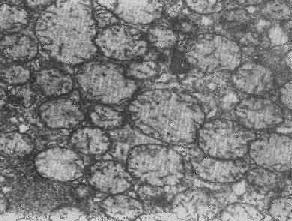

线粒体肿

图1-9 线粒体肿

2.大小改变 细胞损伤时最常见的改变为线粒体肿大。根据线粒体的受累部位可分为基质型肿胀和嵴型肿胀二种类型,而以前者为常见。基质型肿胀时线粒体变大变圆,基质变浅、嵴变短变少甚至消失(图1-9)。在极度肿胀时,线粒体可转化为小空泡状结构(图1-10,图1-11)。此型肿胀为细胞水肿的部分改变。光学显微镜下所谓的浊肿细胞中所见的细颗粒即肿大的线粒体。嵴型肿较少见,此时的肿胀局限于嵴内隙,使扁平的嵴变成烧瓶状乃至空泡状,而基质则更显得致密。嵴型肿胀一般为可复性,但当膜的损伤加重时,可经过混合型而过渡为基质型。

线粒体为对损伤极为敏感的细胞器,其肿胀可由多种损伤因子引起,其中最常见的为缺氧;此外,微生物毒素、各种毒物、射线以及渗透压改变等亦可引起。但轻度肿大有时可能为其功能升高的表现,较明显的肿胀则恒为细胞受损的表现。但只要损伤不过重、损伤因子的作用不过长,肿胀仍可恢复。